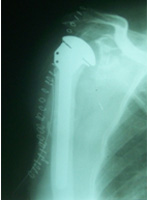

SHOULDER REPLACEMENT